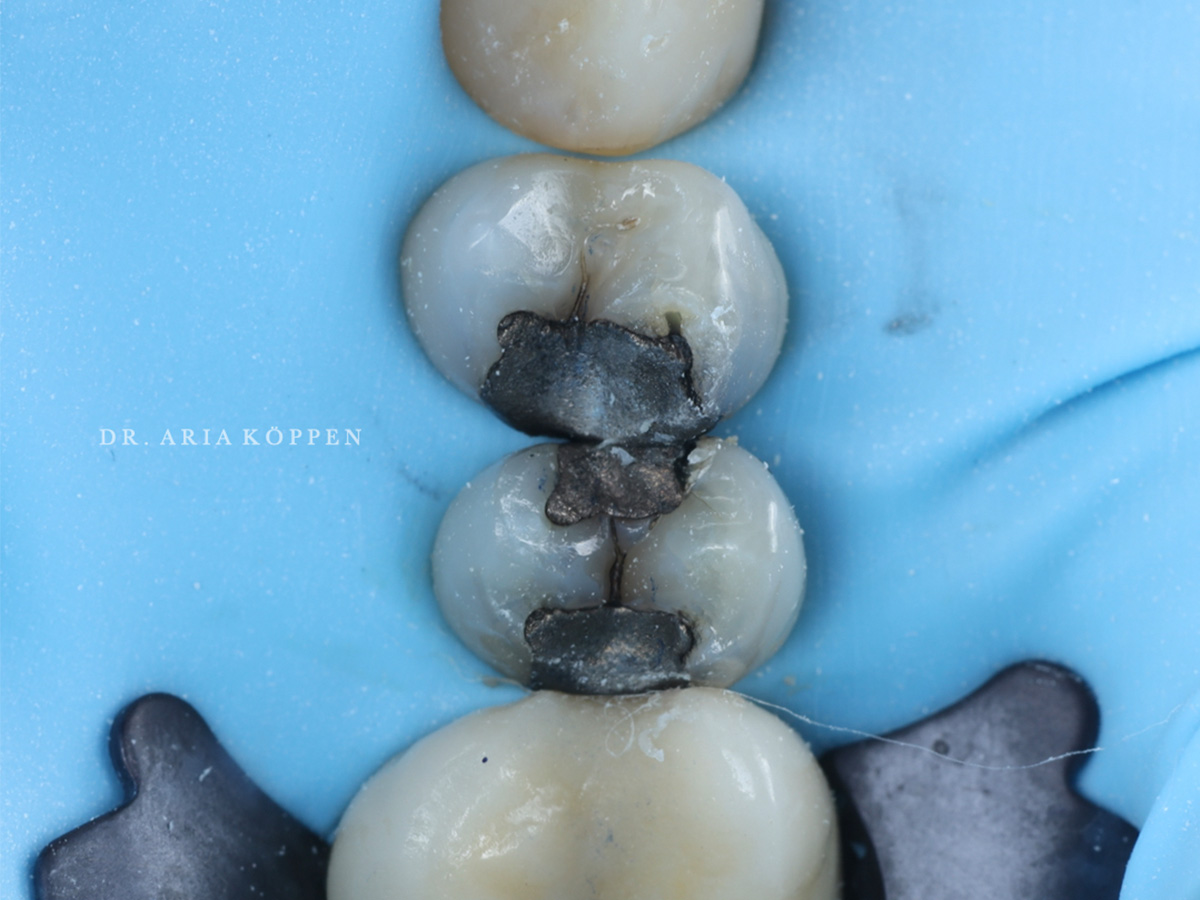

Abbildung 1

Bei dem Patienten wurden kariöse Läsionen unter den bestehenden Amalgamrestaurationen an den Zähnen 14 und 15 diagnostiziert.

Abbildung 2

Nach örtlicher Betäubung regio 14, 15 wurde zur Sicherstellung einer trockenen Arbeitsumgebung ein Kofferdam (Isodam Medium) angelegt und invertiert.